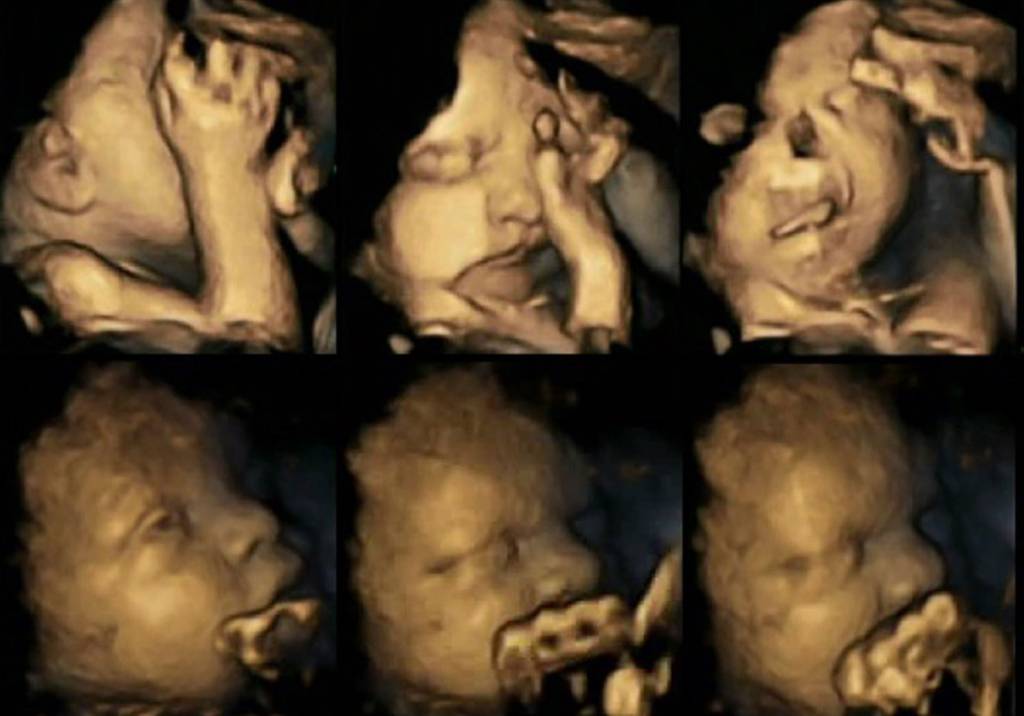

Estudo mostra em imagens como o cigarro afeta o bebê durante a gravidez